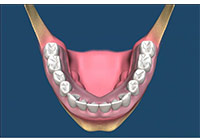

齒槽骨在牙齒拔除後的兩到三年,會面臨 40%-60%的萎縮,之後還會有每年 0.5%-1%後續的骨喪失,因此,一旦缺牙後若沒有儘快處理,患者日後將面臨齒槽骨萎縮引起的義齒製作困難及美觀問題。使用骨質增生膠原蛋白,來處理拔牙後的傷口。此材料適用的範圍不僅用於拔牙後傷口,所有顎骨中的病灶於手術後皆建議使用。牙科專用的3D電腦斷層攝影;與傳統醫療電腦斷層相比較,輻射劑量只有一般電腦斷層的1/50;切片厚度一般醫療電腦斷層是2.0公厘,牙科3D電腦斷層則只有0.1公厘,就診當天馬上拍攝電腦斷層,馬上獲得立體影像(圖01-04)

圖1